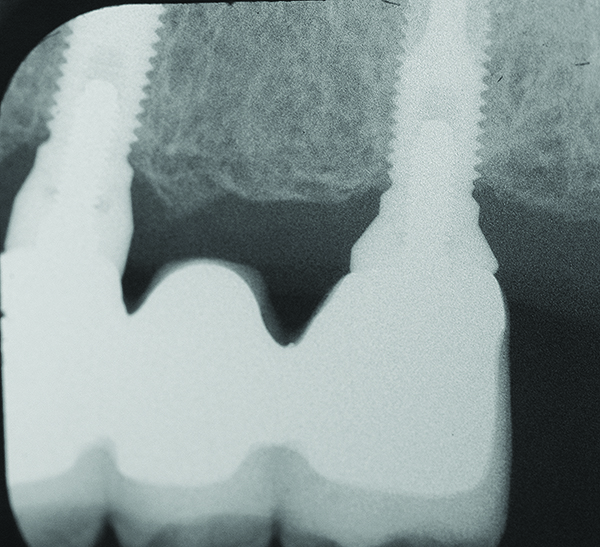

Fig 1 through Fig 6. Periapical radiographs of a 52-year-old man who received a fixed porcelain-fused-to-metal reconstruction supported by abutments attached to externally hexed dental implants. Fig 1 through Fig 3 are at initial prosthesis placement: maxillary right (Fig 1), textured surfaced threaded titanium implants at site Nos. 2, 4, and 6; maxillary anterior (Fig 2), implants at site Nos. 7 through 9; maxillary left (Fig 3), implants at site Nos. 12 and 14. Fig 4 through Fig 6 are 10 years post-insertion of the prosthesis: maxillary right (Fig 4), maxillary anterior (Fig 5), and maxillary left (Fig 6). Note minimal to no bone loss radiographically around the implants 10 years post-insertion of prosthesis.